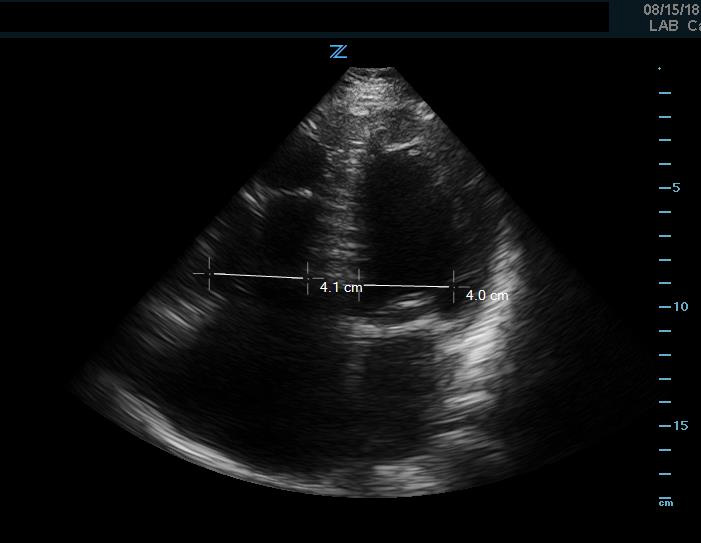

Right ventricular strain

If an undifferentiated hypotensive patient is found to have right ventricular dilatation or strain, this points to an obstructive cause of shock such as pulmonary embolism. This can be detected by looking at right ventricular size, which is best assessed using side-by-side comparison of the LV and RV in the apical 4 chamber view. This can be roughly assessed qualitatively or by measuring the width of the RV and LV at a level 1cm above the tricuspid annulus (Figure 9). Under normal circumstances the RV should be <60% the size of the LV. A ratio of RV:LV greater than 1:1 can be suggestive of right ventricular strain or failure as cause of hypotension.

Figure 9. Apical 4 chamber view. Image of increased RV-LV ratio, approaching 1-1, indicative of severe RV strain.